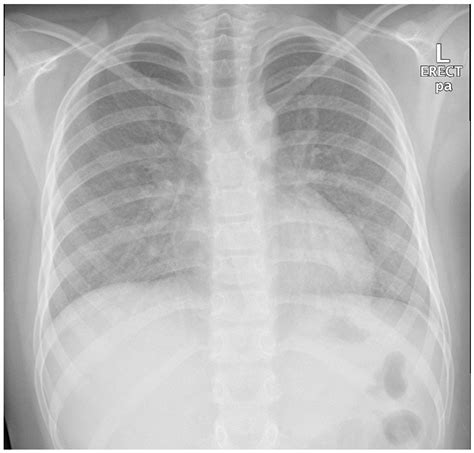

• Chest X-ray or CT scan

• bird fancier lung x ray

• bird fancier's lung radiology